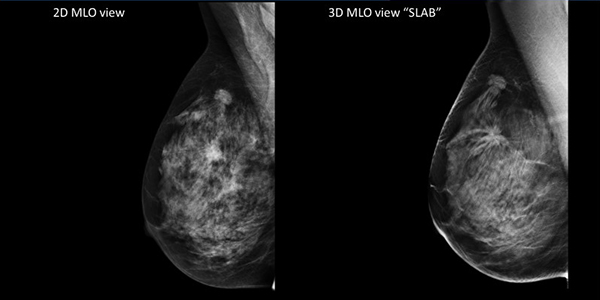

3Dマンモグラフィ撮影

3Dマンモグラフィ撮影は、乳房を多方向から撮影し、立体的な画像で乳腺の状態を確認できる検査です。

乳がんの早期発見を目的とした検査で、乳腺が密な方にも有効とされています。定期的な乳がんチェックとして安心して受けられる検査です。